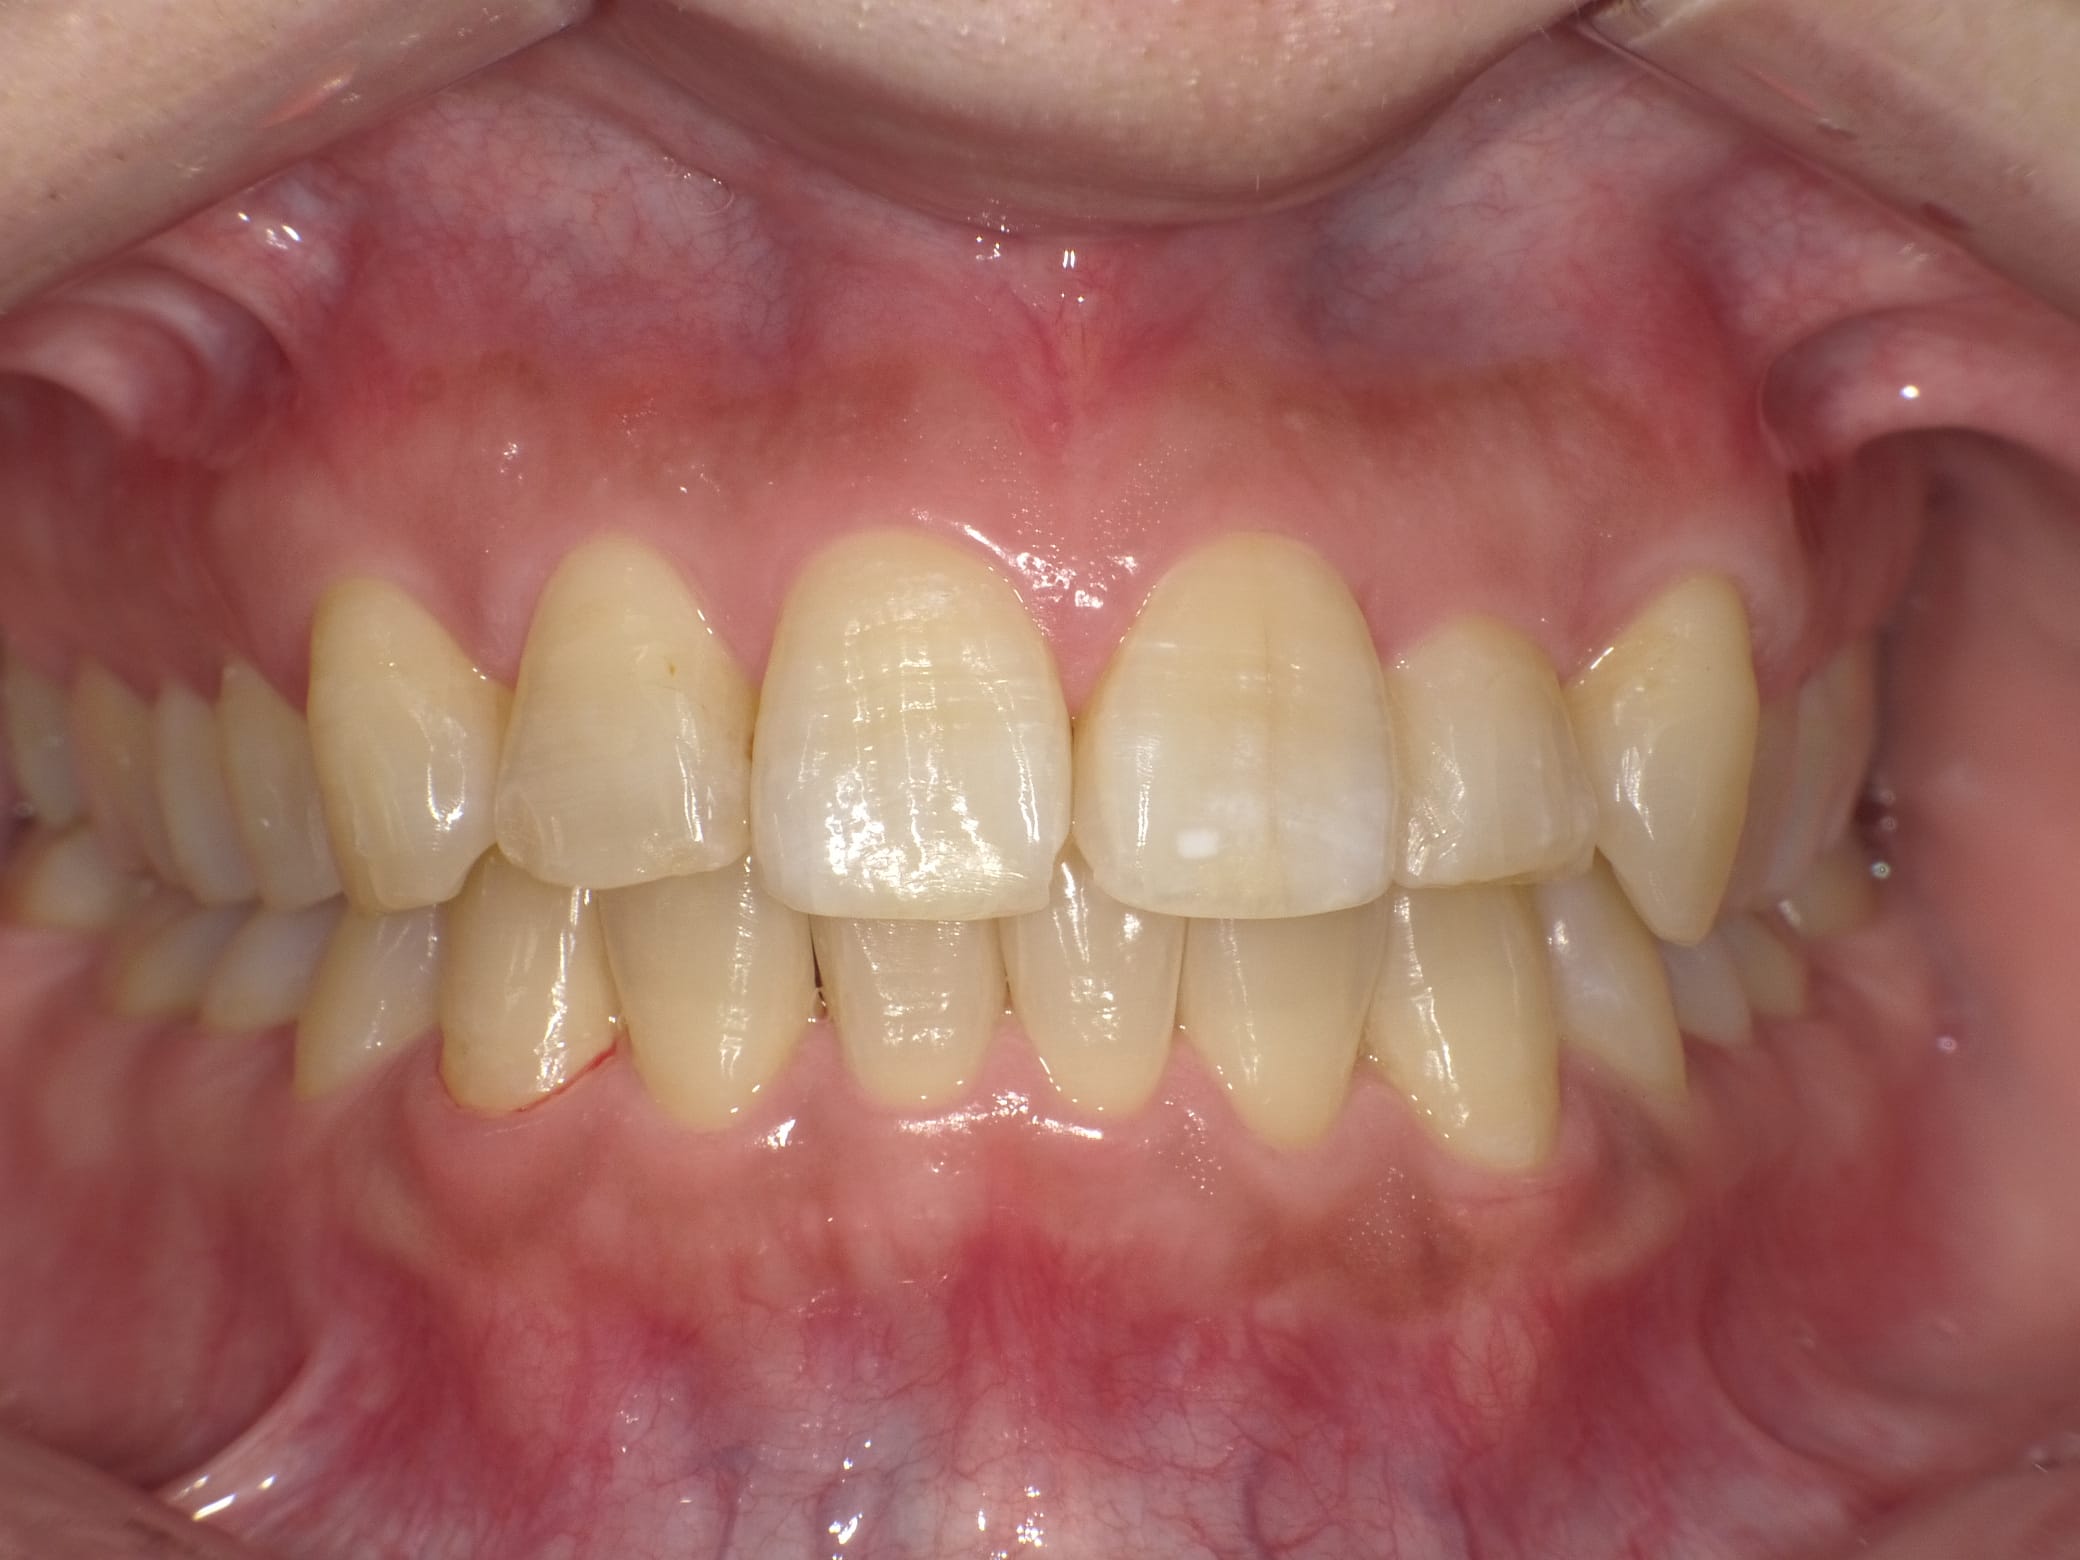

Case001 – セラミック矯正

「昔から歯並びが気になっているので治したいが、もうすぐ海外に行くので時間がない」

「可能な限り安く、できるだけ自分の歯は削らないで綺麗に見えるようにして欲しい」

という患者様の症例です。

【治療内容】

上4本下4本 オールセラミッククラウン

【治療期間】

1ヶ月

【治療費】

840,000円

担当:理事長 佐藤悠野

Before写真にある下顎の最も前に出ている前歯を矯正なしで治療するために、神経をとる必要があった